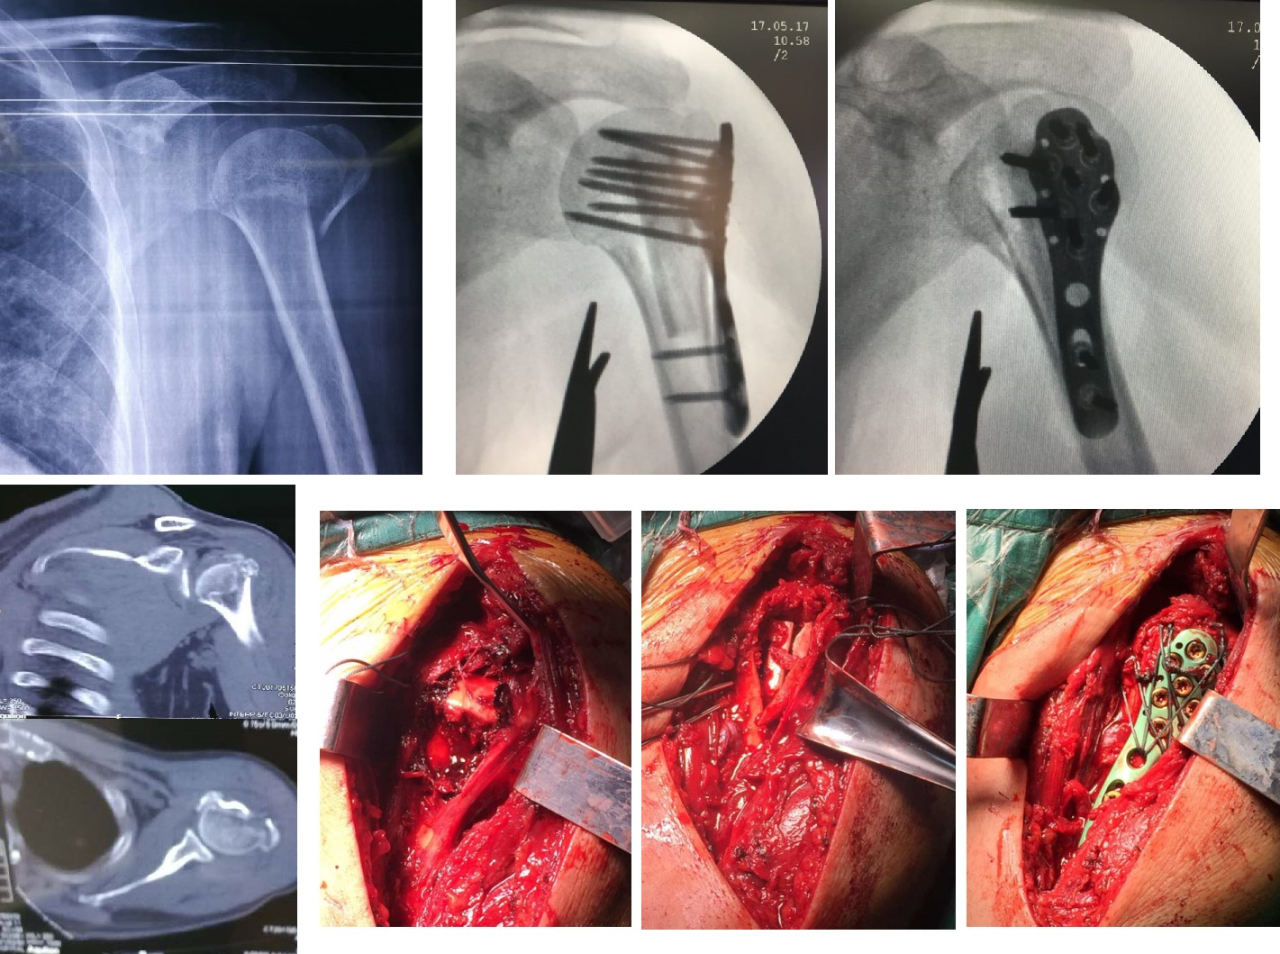

Рисунок 1. 65-летняя женщина с 4-частным переломом места прикрепления проксимального аддуктора плечевой кости и фиксацией аллотрансплантата малоберцовой пластиной имплантата с разрезом и изменением положения.